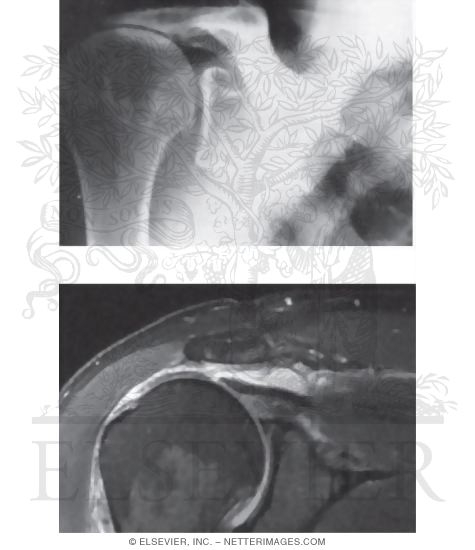

X-ray Findings In Rotator Cuff Tears / Impingement Syndrome : Wheeless

X-ray Findings in Rotator Cuff Tears / Impingement Syndrome : Wheeless www.wheelessonline.com

rotator impingement bursa sclerosis subacromial tuberosity mri radiographs